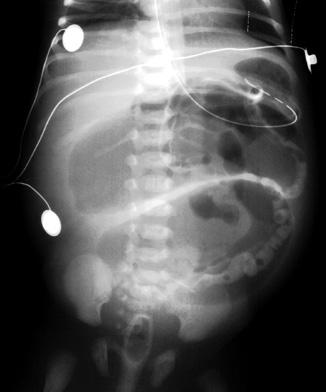

Barium enema demonstrates unused microcolon in a patient with distal ileal atresia. |